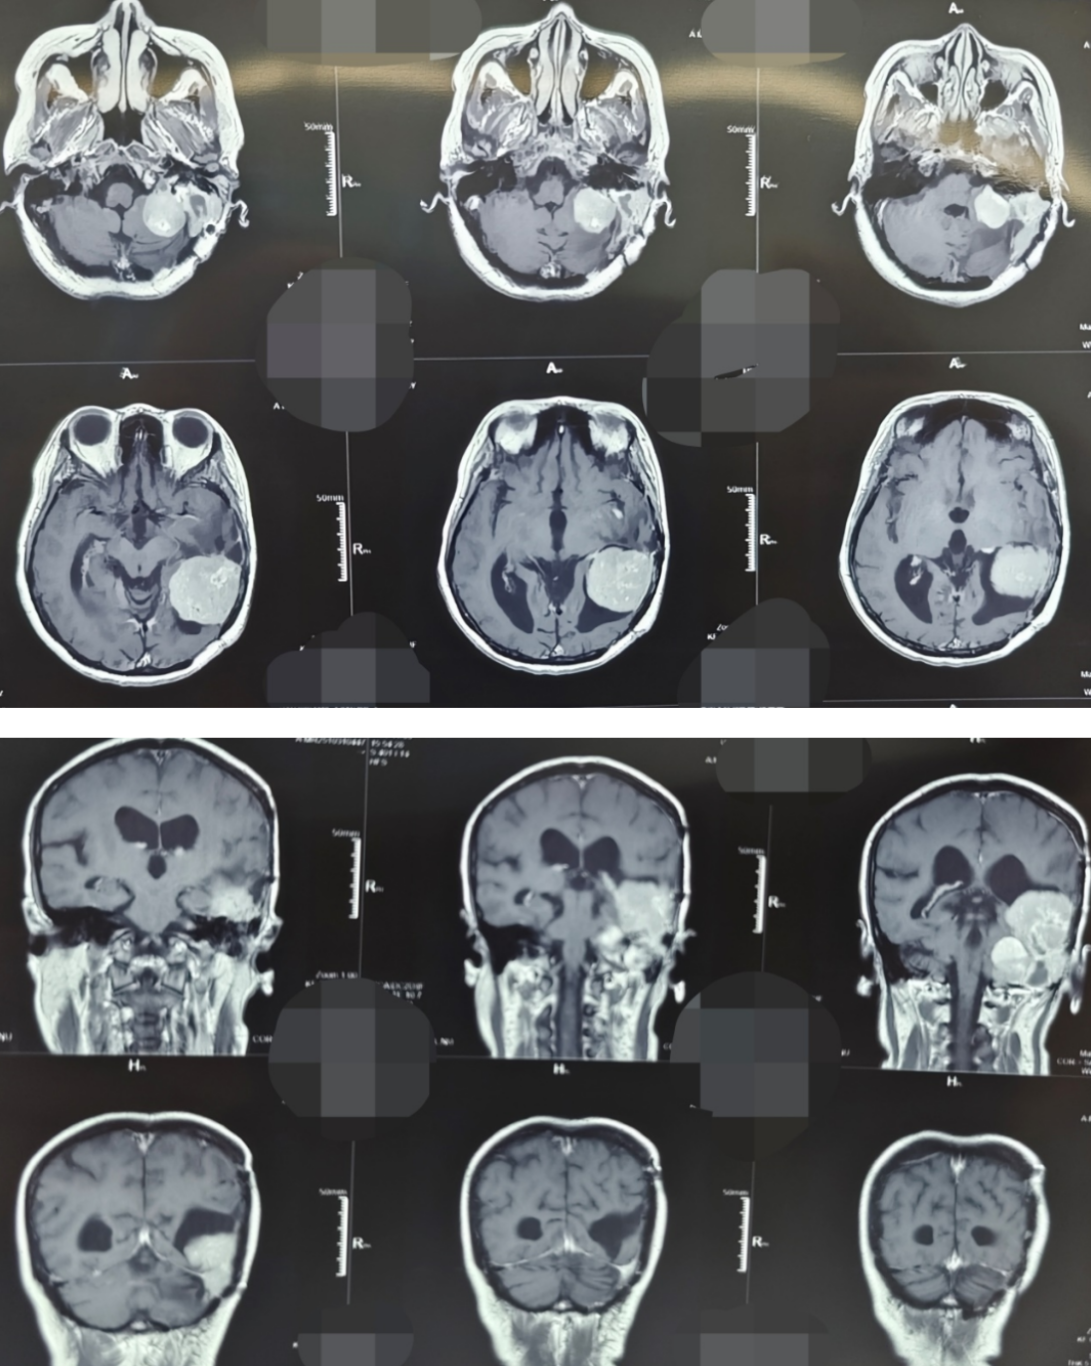

45岁的张女士,因“头晕、耳鸣伴听力下降”来到西安市红会医院就诊。她曾在2011年和2017年两次因颅内血管周细胞瘤于外院接受开颅手术治疗,并进行术后放化疗。此次入院后影像学检查显示,肿瘤在左侧颞部及桥小脑角区复发。该区域毗邻脑干、面神经、听神经及多条重要血管,素有“生命禁区”之称,手术风险极高。

更为严峻的是,进一步检查发现患者体内存在高度疑似肝脏转移灶,提示疾病可能已进入晚期;同时合并严重贫血、心脏电生理异常等多种并发症。病情复杂、风险叠加,任何环节处置不当均可能导致严重后果。